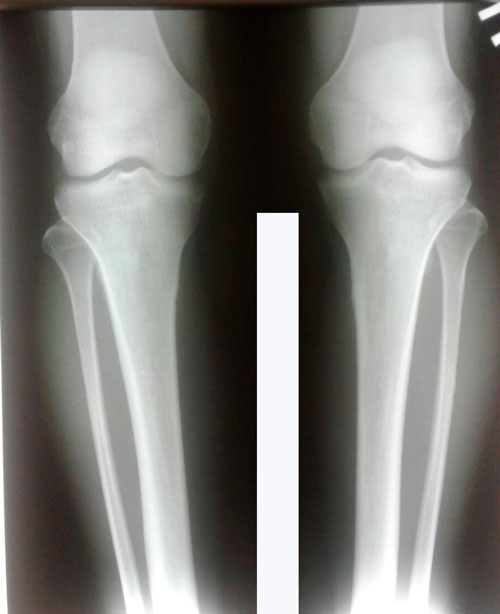

Дата операции 06.07.2017г.

Дата снятия аппаратов 18.09.2017г.

Срок лечения 72 дня.